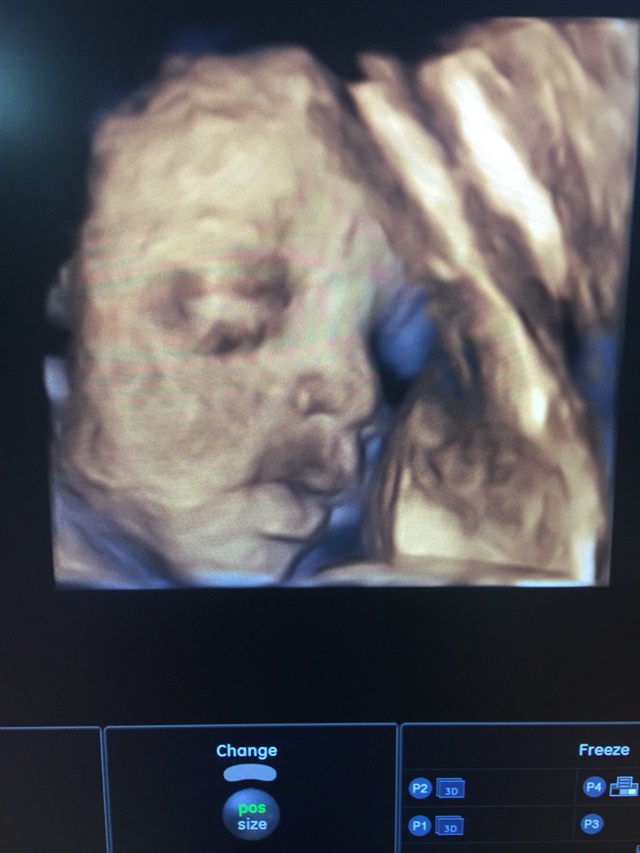

还打哈欠……这么萌的嘛

好可爱啊,还在打哈欠😁😁😁